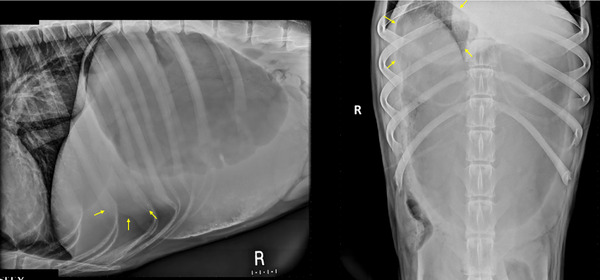

Gastric dilatation and volvulus (GDV) is a life-threatening emergency that requires urgent intervention. Radiographic features associated with 360-GDV in dogs have not been investigated. The aim of this retrospective observational study is to describe radiographic features and clinical variables in dogs affected with 360-GDV and to report agreement rates between different radiologists. We also report the sensitivity and specificity of radiographs to diagnose 360-GDV in dogs. Confirmed 360-GDV cases were retrieved, and the radiographic findings were compared with dogs presenting with gastric dilatation (GD) and 180-GDV. Images were reviewed and graded by three blinded board-certified radiologists. A total of 16 dogs with confirmed 360-GDV were identified. The median age was 10 years old (2-13 years). The sensitivity for detection of 360-GDV ranged between 43.7% and 50%, and the specificity between 84.6% and 92.1%. Interobserver agreement on final diagnosis was substantial (Kappa = 0.623; 0.487-0.760, 95% CI). The highest agreement rate was in cases of 180-GDV (87%), followed by the GD cases (72%) and 360-GDV (46%). Severe esophageal distension and absence of small intestinal dilation were the only radiographic features specifically associated with 360-GDV. A similar pyloric position was found between GD and 360-GDV. Additional radiographic variables that could help differentiate GD from 360-GDV include the degree of gastric distension and the peritoneal serosal contrast. Two cases with 360-GDV were misdiagnosed by the three radiologists as GD. In conclusion, radiographically, 360-GDV cases can reassemble GD and vice versa. Radiologists and clinicians should be aware of the low sensitivity of radiographs for the detection of 360-GDV.

胃扩张和胃内卷(GDV)是一种危及生命的急症,需要紧急干预。目前尚未研究过与犬 360-GDV 相关的放射学特征。这项回顾性观察研究旨在描述受 360-GDV 影响的犬的放射学特征和临床变量,并报告不同放射科医生之间的一致率。我们还报告了诊断 360-GDV 的敏感性和特异性。我们对确诊的 360-GDV 病例进行了检索,并将其影像学结果与胃扩张(GD)和 180-GDV 病例进行了比较。由三位具有盲人资格的放射科医师对图像进行审查和分级。共有 16 只狗确认患有 360-GDV。中位年龄为 10 岁(2-13 岁)。检测 360-GDV 的灵敏度介于 43.7% 和 50% 之间,特异性介于 84.6% 和 92.1% 之间。观察者之间对最终诊断的一致性很高(Kappa = 0.623; 0.487-0.760, 95% CI)。一致率最高的是 180-GDV 病例(87%),其次是 GD 病例(72%)和 360-GDV 病例(46%)。食管严重扩张和无小肠扩张是与 360-GDV 特别相关的唯一影像学特征。GD 和 360-GDV 的幽门位置相似。有助于区分 GD 和 360-GDV 的其他影像学变量包括胃扩张程度和腹膜浆膜对比度。有两例 360-GDV 病例被三位放射科医生误诊为 GD。总之,从影像学角度看,360-GDV 病例可与 GD 病例重合,反之亦然。放射科医生和临床医生应该意识到,放射线检查对 360-GDV 的检测灵敏度较低。